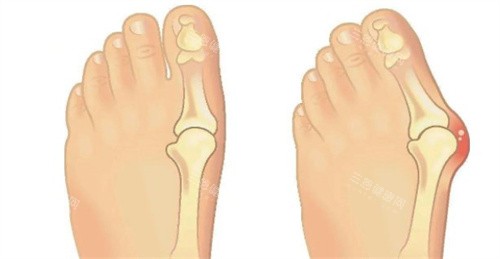

身边好多人受拇指外翻困扰 —— 穿鞋磨脚、走路疼,有的甚至影响运动和日常。

基本情况:拇指叠在第二脚趾上,穿鞋挤得疼,走路都得瘸着,影响生活

亲身感受:术前更担心矫正后脚趾还叠着,苏医生说会调整到位,术后拆线一看,脚趾真的变直了!术后前 4 天肿得强,每天冰敷 3 次,肿消得快。

4 个月后走路正常,再也不用瘸着了。